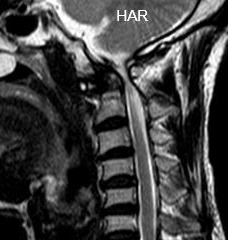

59岁的患者黄先生1年前开始出现四肢麻木、乏力,并逐渐出现行走困难及大小便障碍,因其为低保户,经济困难,一直未正规治疗,后症状逐渐加重,入院前已经出现四肢无力以及大小便困难,收入我院骨科一区治疗。入院检查MR提示“寰枢椎脱位、椎管狭窄、脊髓受压”。

术前与术后对比图